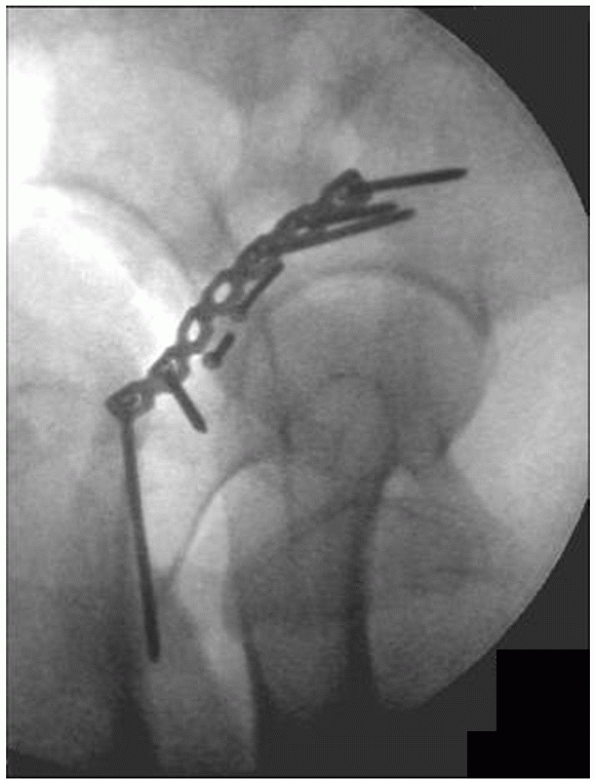

FIGURE 45-4

A 55-year-old obese woman involved in a motor vehicle accident had a right acetabular fracture and history of hip dislocation. An intraoperative fluoroscopic view (A) prior to surgical intervention shows a femoral head fracture (arrows), a small posterior wall fracture (arrowhead), and a subluxated hip joint. The intraoperative fluoroscopic view (B) after reduction and fixation of both fractures, performed at the same operative intervention using a trochanteric-flip osteotomy surgical approach35,38 is shown prior to reattachment of the trochanteric osteotomy. (Copyright Berton R. Moed, MD.) |

displaced fracture of the femoral head may be present, especially in

association with a posterior fracture-dislocation.73 These fractures are usually treated at the time of acetabular fracture fixation (Fig. 45-4).